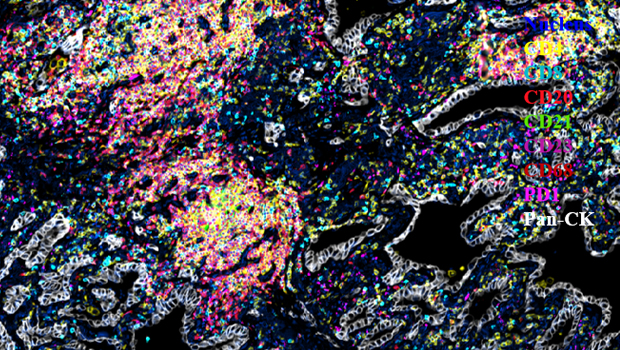

服务案例

Nucleus,CD4,CD8,CD20,CD21,CD23,CD68,PD-1,Pan-CK